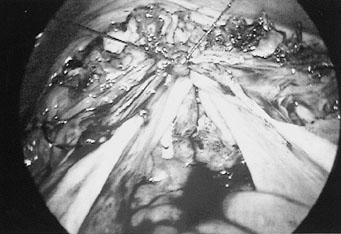

3

Eικόνα 3. Σύγκλιση του κολπικού

κολοβώματος με ράμμα που περιλαμβάνει και τους ιερομητρικούς συνδέσμους.